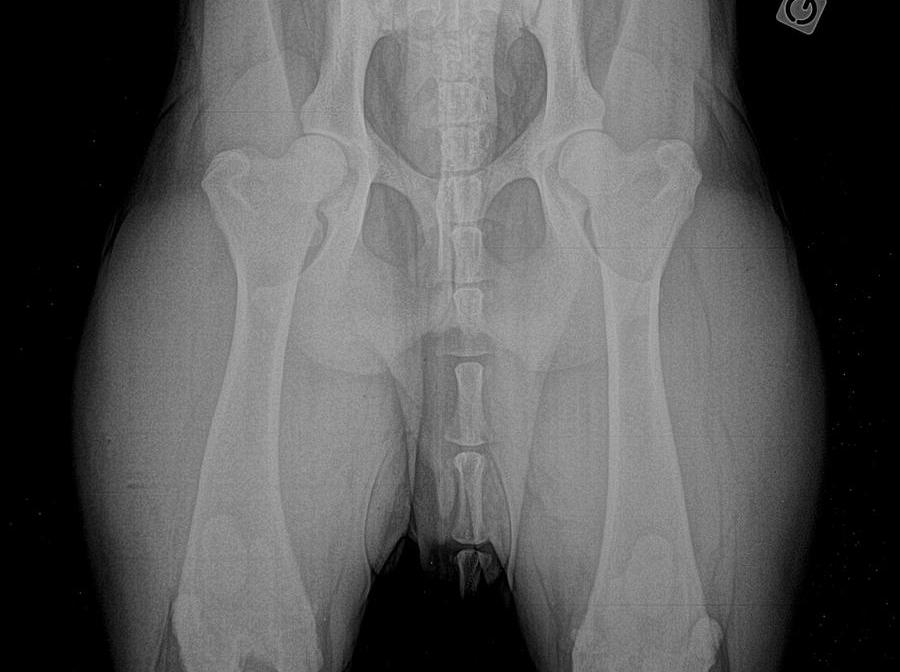

HIPS

XRails

Report